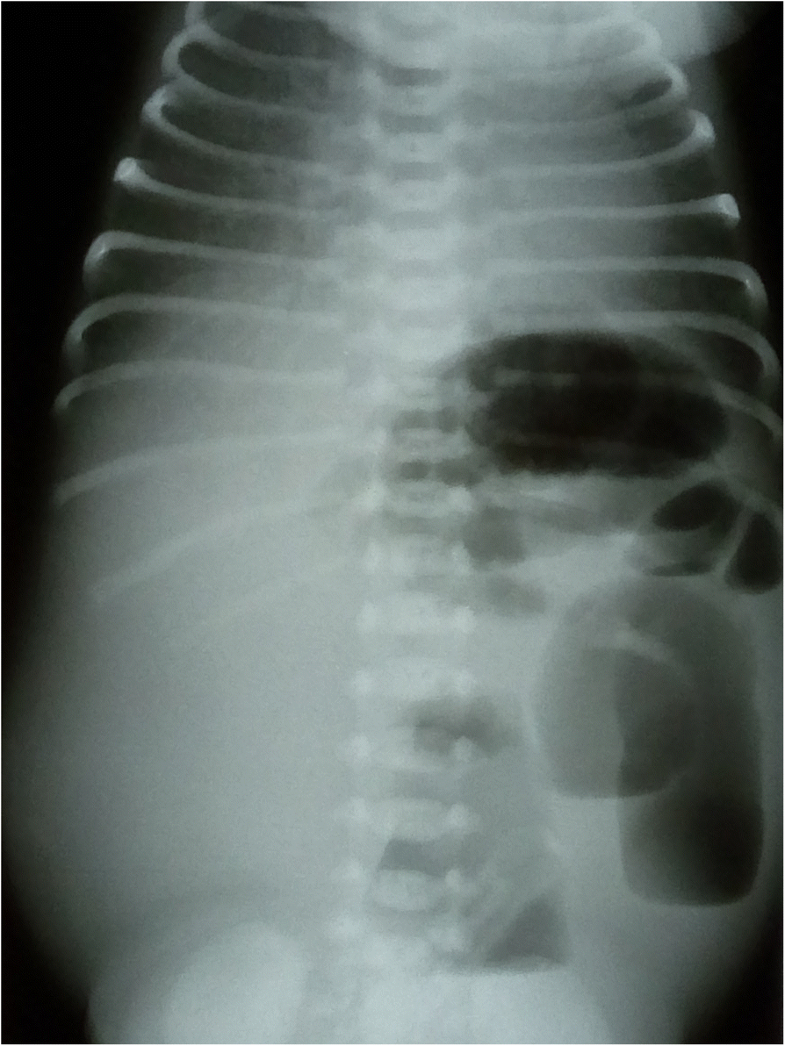

Congenital ChlorideLosing Diarrhea in Saudi Children Annals of Saudi

From www.annsaudimed.net

Congenital ChlorideLosing Diarrhea in Saudi Children Annals of Saudi Chloride Levels Diarrhea Typically, hyperchloremia does not cause specific. what are the symptoms of hyperchloremia? Many factors can cause an abnormal level. chloride blood tests check to make sure you have appropriate levels of chloride in your blood to be healthy. Your deficiencies and excesses will vary depending on the cause of the imbalance and come with their own set of. Chloride Levels Diarrhea.